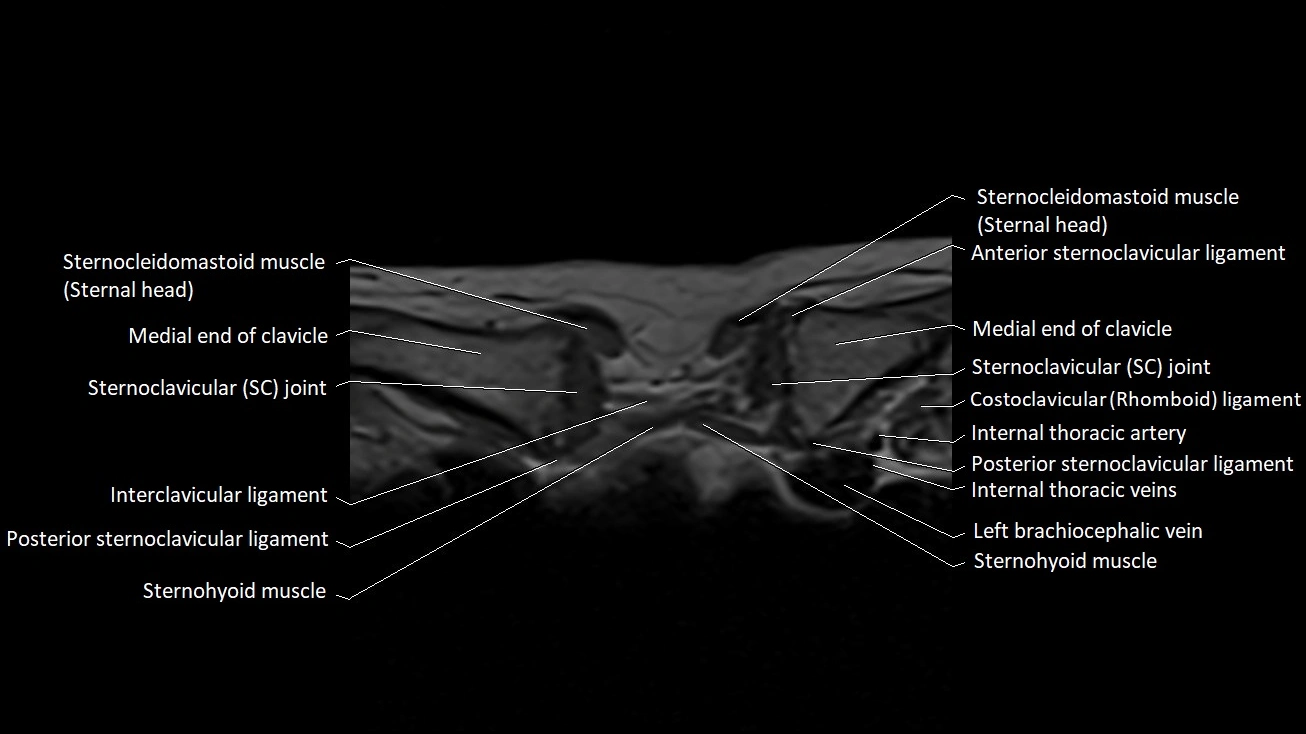

Anterior sternoclavicular ligament

The anterior sternoclavicular ligament (ASCL) is the thickened anterior portion of the joint capsule of the sternoclavicular (SC) joint, reinforcing the articulation between the sternal end of the clavicle and the manubrium of the sternum. As one of the key stabilizers of the SC joint, it prevents excessive anterior and superior translation of the clavicle during upper limb movement.

The ligament spans obliquely from the anterior surface of the manubrium to the anterior aspect of the medial clavicle. Its strength is essential for shoulder girdle stability, as the SC joint serves as the only true synovial articulation connecting the upper limb to the axial skeleton.

Location and Structure

• Position: Lies on the anterior surface of the sternoclavicular joint, connecting the manubrium to the sternal end of the clavicle.

• Orientation: Runs obliquely superolaterally from the sternum toward the clavicle.

• Composition: Dense fibrous connective tissue forming the anterior reinforcement of the SC joint capsule.

• Thickness: Broad and strong, blending with the surrounding capsule and interclavicular ligament superiorly.

Relations

• Anteriorly: Skin, superficial fascia, sternocleidomastoid muscle (sternal head).

• Posteriorly: SC joint capsule, articular disc, and synovial space.

• Superiorly: Interclavicular ligament.

• Inferiorly: Manubrial surface and upper costoclavicular region.

• Laterally: Medial clavicle.

• Medially: Manubrium of the sternum.

MRI Appearance

T1-weighted images

• Ligament appears as a low-signal (dark) linear band on the anterior aspect of the SC joint.

• Surrounding fat appears bright, providing contrast with the ligament.

• The clavicle and manubrium show normal cortical low signal with bright fatty marrow internally.

MRI images

image